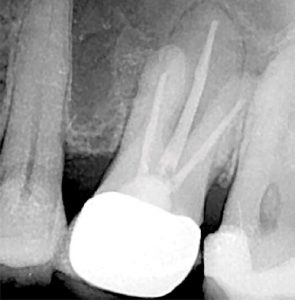

A two-dimensional intraoral radiograph revealed a prior history of root canal therapy and a porcelain-fused-to-metal (PFM) crown (both completed approximately 10years ago) (Figure 2).